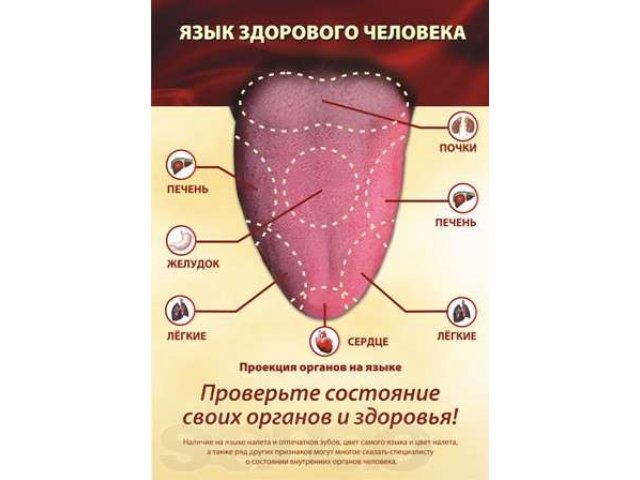

Литературный язык и его нормы: визуальное пособие

Раздел: Фотопанорама